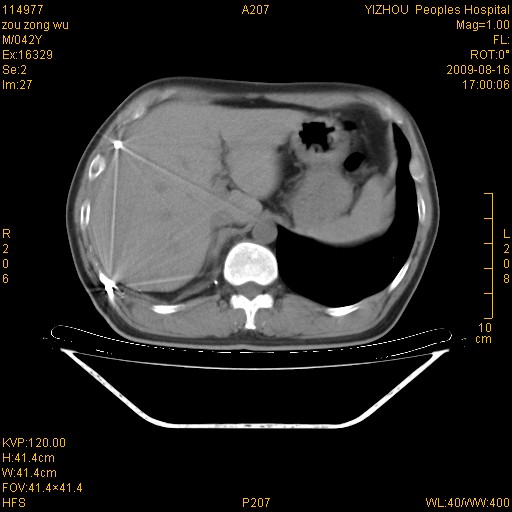

以下是引用zjzjr在2009-8-17 10:42:00的发言:[br]右侧间质性肺炎伴纤维化,右肺下叶肺囊肿伴感染(不除外外伤后引起),右肺野及胸壁软组织\\肝内见多发斑点状,中枪了吧.右侧胸膜肥厚\\粘连.